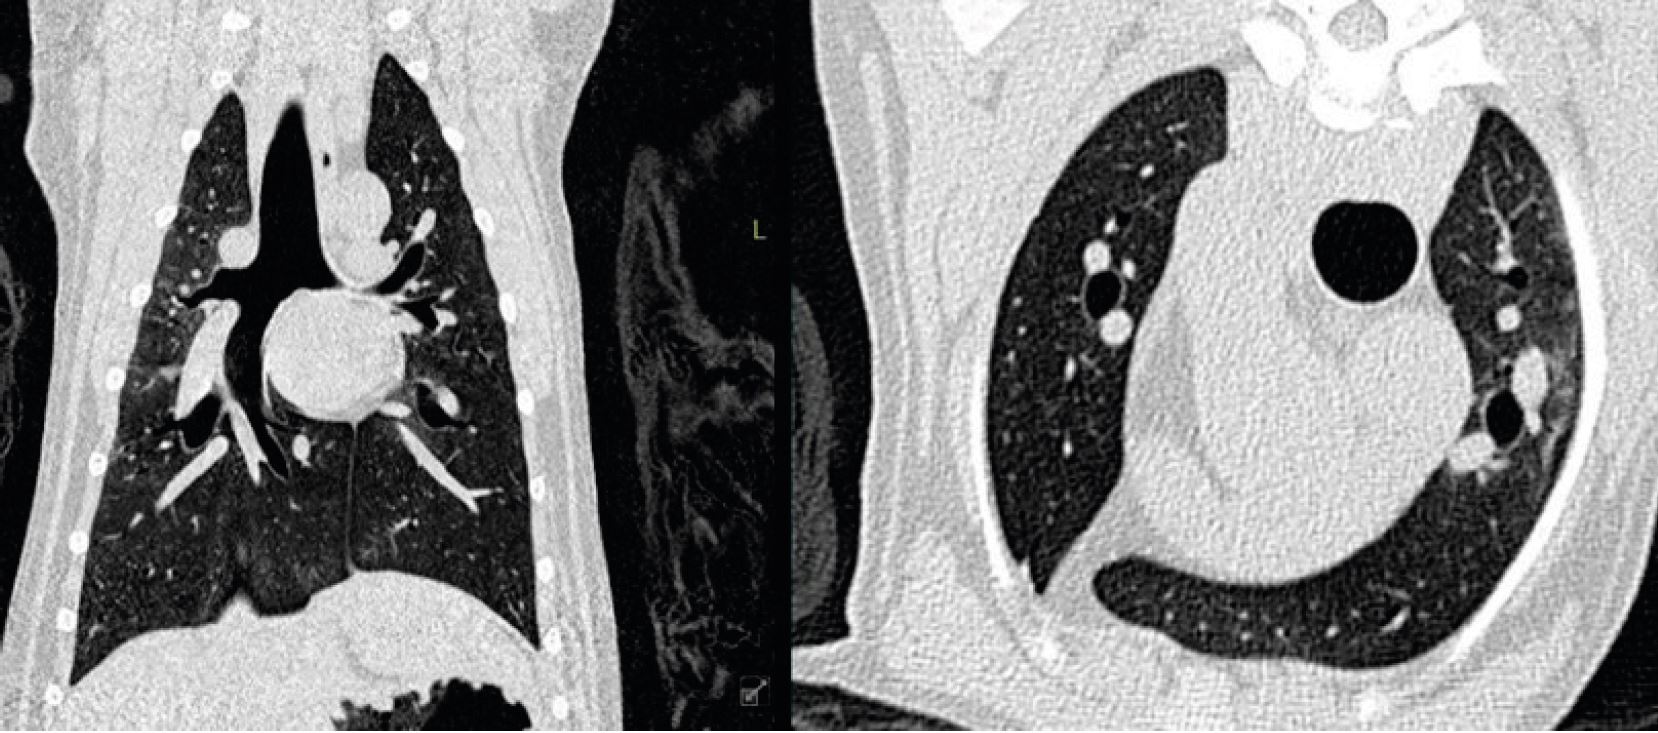

Цікавим виявленням було те, що всі КТ-сканування показали чіткі інтерстиціальні та альвеолярні зміни в легенях (мал. 4). Зверніть увагу на відмінності від сканування нормальних легенів собаки (мал. 5). Швидше за все зміни були викликані ателектазом внаслідок реакції апное, пов’язаної з анестезією. Тюлені були інтубовані та штучно вентильовані, але лише після того, як вони були достатньо анестезовані після внутрішньом’язової ін’єкції. Це могло спричинити пригнічення дихання і, отже, зміни в легенях. Ця гіпотеза підтверджується тим фактом, що зміни частково зникли на другому комп’ютерному скануванні Елвіса, яке було зроблено приблизно через 15 хвилин після першого сканування (мал. 6).

Малюнок 4: Ф ронтальне MPR і аксіальне КТ-зображення у вікні кістки Вінсента показують дифузні інтерстиціальні та альвеолярні інфільтрати. Ці знахідки різною мірою були помічені в усіх трьох тюленях.

Малюнок 5: Фронтальні та аксіальні зображення здорової собаки демонструють нормальний вигляд легеневої паренхіми.

Малюнок 6: Фронтальні зображення грудної клітини Елвіса на одному рівні показують зменшення інтерстиціальних/альвеолярних змін між серіями сканування. Праве сканування було зроблено через 15 хвилин після лівого.